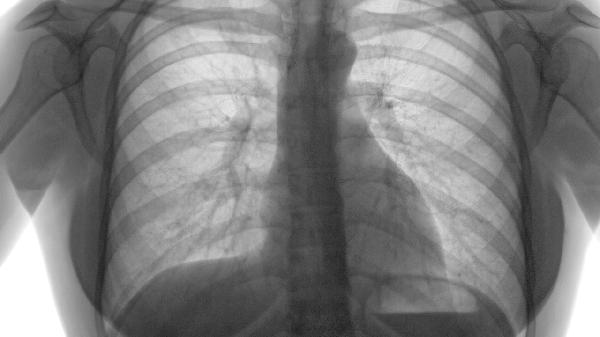

肺气肿的特效药有哪些

肺气肿的治疗主要依赖药物缓解症状、改善肺功能,常用特效药包括支气管扩张剂、糖皮质激素和祛痰药。支气管扩张剂如沙美特罗、福莫特罗可缓解气道痉挛;糖皮质激素如布地奈德、氟替卡松能减轻炎症;祛痰药如氨溴索、乙酰半胱氨酸帮助排痰。